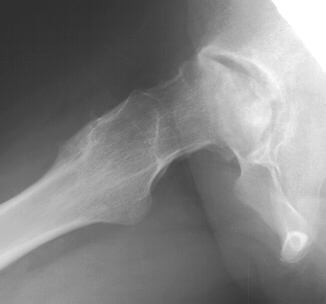

F/U age 14 with a 2mo. history of left hip pain, aggravated with activity.

Clinical findings were not suggestive of infection. She was diagnosed with

AVN of the left femoral head. Management consisted of NSAIDS, restricted

wt. bearing.

Two months later she under went a left hip core decompression and bone

grafting without problem

Rehabilitation was steady maintaining a restriction on wt. bearing and

encouraging range of motion. She had a significant decrease in her pain

although the radiographs showed progressive collapse.

Four years later, she is able to ambulate without any aids but complains

of a dull ache in her left hip and a limitation in rotation

.

- Radiological Changes (Chung etal)

- Group 1 - < 8yo similar to Legg-Calve-Perthes

- usually regenerate without significant disability, prognosis is worse

in the older adolescent

- Group 2 - Resembles osteochondritis dissecans

- poor healing

- Group 3 - Massive necrosis; adult patient